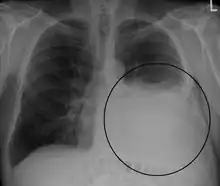

A large left-sided pleural effusion as seen on an upright chest X-ray

A pleural effusion is usually diagnosed on the basis of medical history and physical exam, and confirmed by a chest X-ray. Once accumulated fluid is more than 300 mL, there are usually detectable clinical signs, such as decreased movement of the chest on the affected side, dullness to percussion over the fluid, diminished breath sounds on the affected side, decreased vocal resonance and fremitus (though this is an inconsistent and unreliable sign), and pleural friction rub. Above the effusion, where the lung is compressed, there may be bronchial breathing sounds and egophony. A large effusion there may cause tracheal deviation away from the effusion. A systematic review (2009) published as part of the Rational Clinical Examination Series in the Journal of the American Medical Association showed that dullness to conventional percussion was most accurate for diagnosing pleural effusion (summary positive likelihood ratio, 8.7; 95% confidence interval, 2.2–33.8), while the absence of reduced tactile vocal fremitus made pleural effusion less likely (negative likelihood ratio, 0.21; 95% confidence interval, 0.12–0.37).[11]

Imaging

A pleural effusion appears as an area of whiteness on a standard posteroanterior chest X-ray.[12] Normally, the space between the visceral pleura and the parietal pleura cannot be seen. A pleural effusion infiltrates the space between these layers. Because the pleural effusion has a density similar to water, it can be seen on radiographs. Since the effusion has greater density than the rest of the lung, it gravitates towards the lower portions of the pleural cavity. The pleural effusion behaves according to basic fluid dynamics, conforming to the shape of pleural space, which is determined by the lung and chest wall. If the pleural space contains both air and fluid, then an air-fluid level that is horizontal will be present, instead of conforming to the lung space.[13] Chest radiographs in the lateral decubitus position (with the patient lying on the side of the pleural effusion) are more sensitive and can detect as little as 50 mL of fluid. Between 250 and 600mL of fluid must be present before upright chest X-rays can detect a pleural effusion (e.g., blunted costophrenic angles).[14]